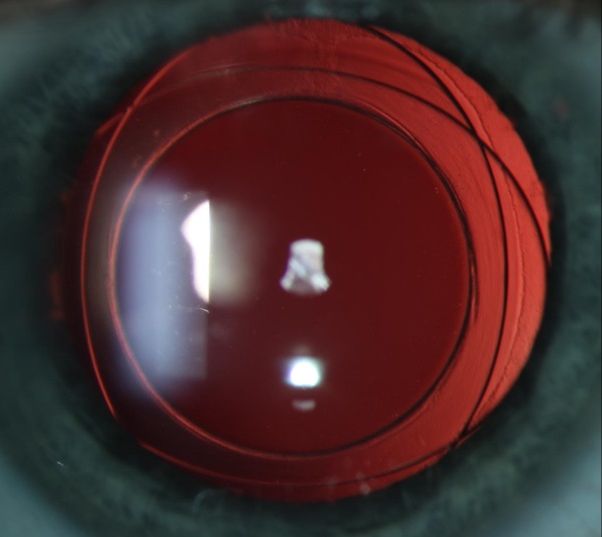

Zur Therapie des Grauen Stars wird in der Regel die eingetrübte natürliche Linse des Auges entfernt und durch eine Kunstlinse (IOL) ersetzt. Die Wahl der IOL erfolgt in Zusammenarbeit mit Ihrem Arzt. In unserer Klinik verwenden wir überwiegend hochwertige Bag-in-the-Lens Kunstlinsen, die das Risiko für die Bildung postoperativer Komplikationen wie Nachstar oder Makulaödem deutlich reduzieren.

Bag-in-the-Lens Linse zur Behandlung der Katarakt